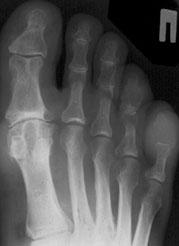

Для диагностики обязательно необходимо провести рентгенографию стопы. Этот метод позволяет выявить костные изменения, разрастания, пограничные дефекты суставных поверхностей, уменьшение суставных щелей, субхондральный склероз костной ткани и наличия кистовидных образований, что дает возможность провести дифференциальную диагностику.

Четвертая степень. Все вышеперечисленные симптомы становятся более выраженными, появляется заметная деформация, болевой синдром может стать невыносимым. В некоторых случаях развивается полное обездвиживание сустава.